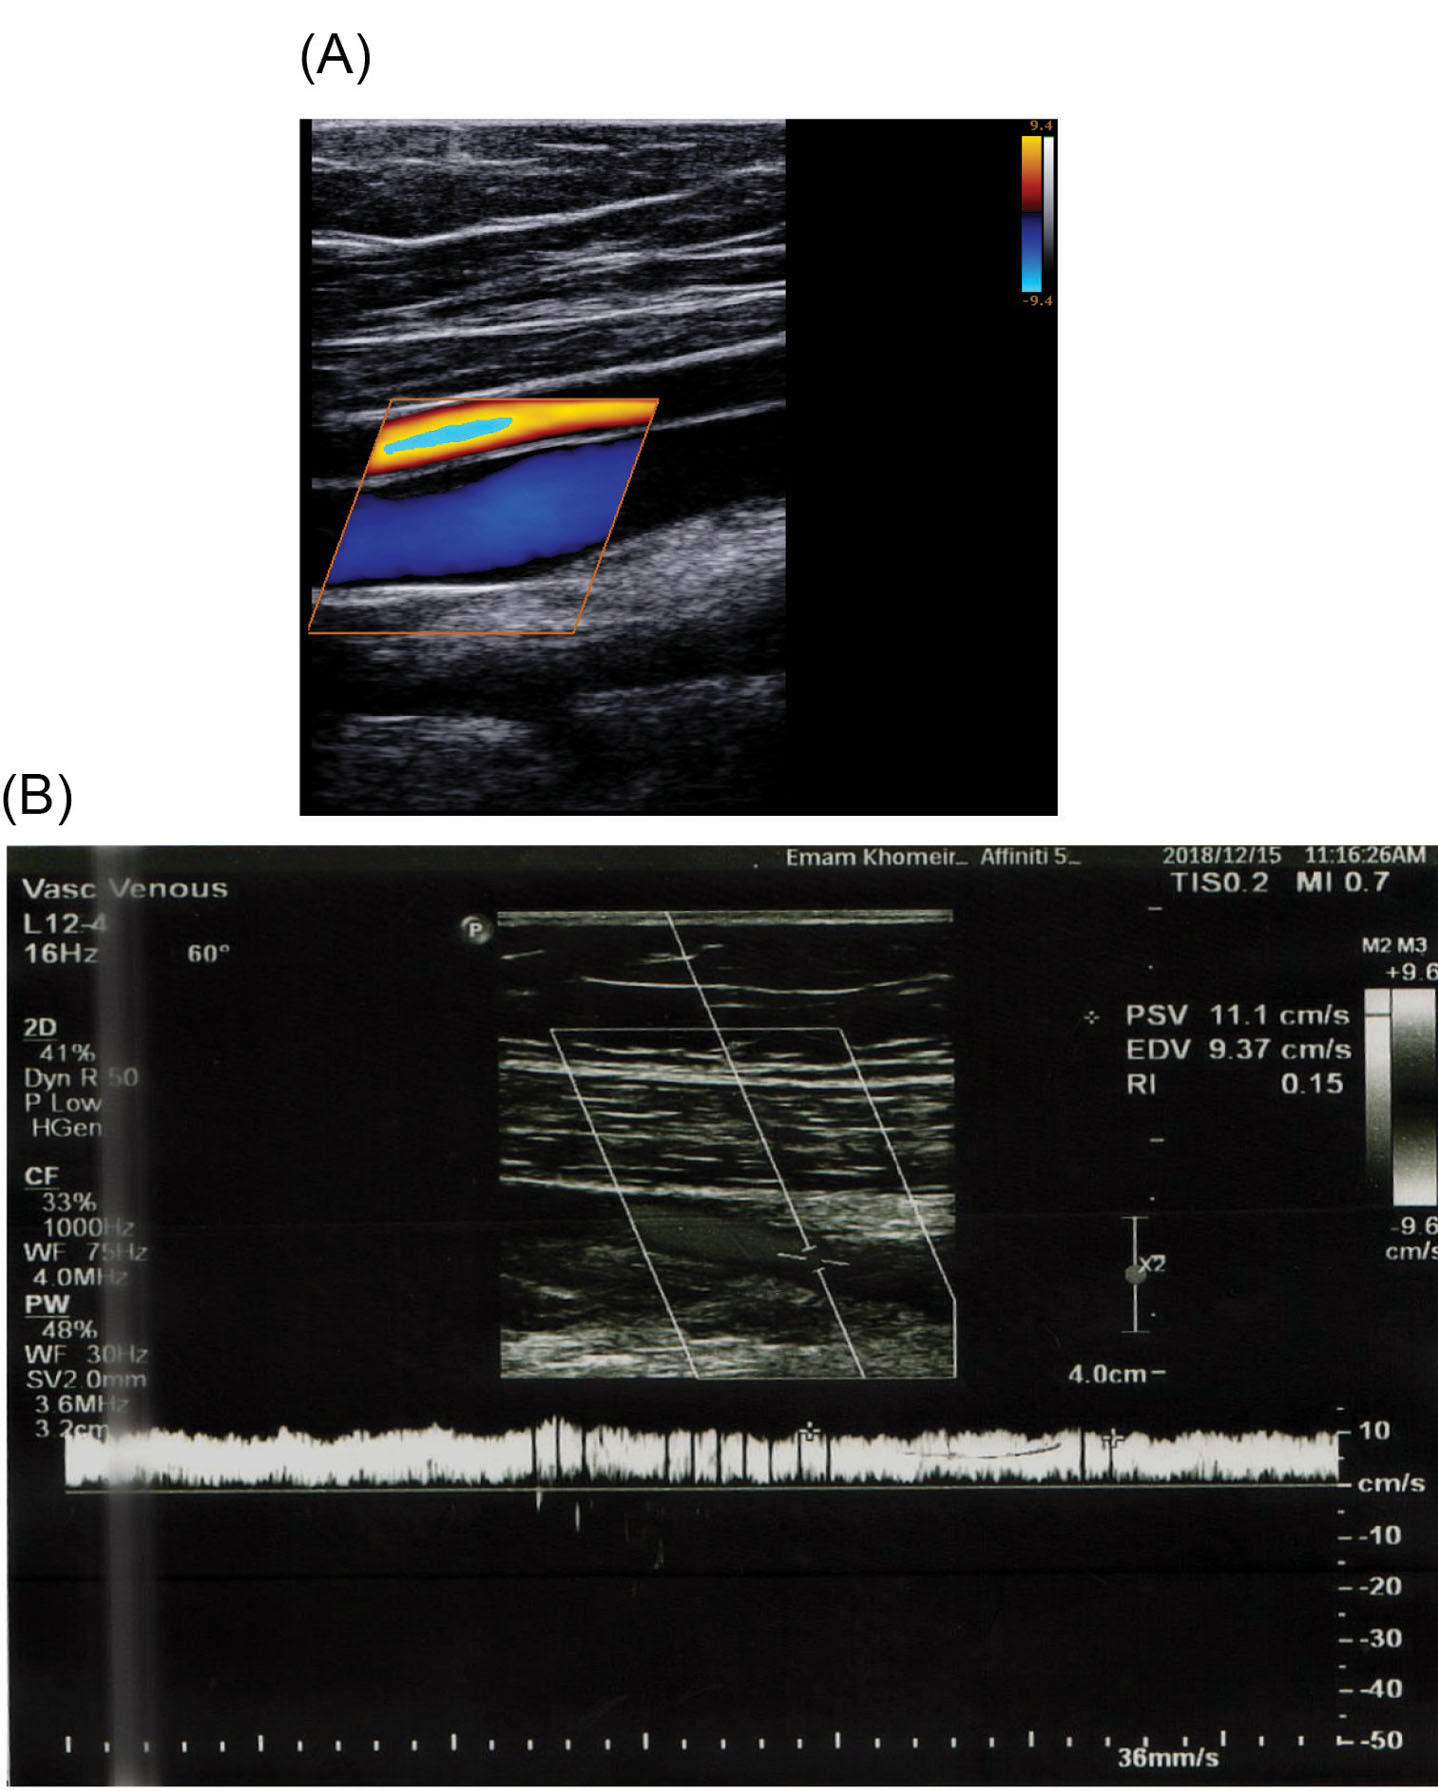

To simulate and validate the obtained results of blood flow through a venous valve, a Doppler Ultrasound image of a 35-year-old person was used (Fig. 1A). The scan was performed with the person in a relaxed supine position and the flow velocity was measured at a point between the valve leaflets of the femoral vein. The computational geometry (Fig. 1B) was designed based on the real sample of Fig. 1A. Blood (Domain 5) is considered as Newtonian fluid, and the governing equations are solved for laminar regime.

Fig. 1.

Applied geometry of the present work. (A) Doppler Ultrasound image of a venous valve in the closed position. (B) Geometry for present work.

Blood enters the inlet region with a maximum periodic velocity of 10 cm/s. In the first instance, the valves are closed. Blood flow applies stress to the valves and consequent strain results in the valve opening through time. It is needed to validate the obtained results of numerical simulation, therefore a series of experiments were carried out by Doppler ultrasound image of a healthy thirty-five-year-old person with no history of vascular disease which is shown in Fig. 3A and 3B. The velocity magnitude of blood passing through the valve was obtained at three different points along the centerline of the femoral vein with the subject in supine position and the data was compared with numerical results.

In vivo measurements. (A) Doppler Ultrasound image of the vein. (B) Velocity magnitude at the point between leaflets obtained by Doppler Ultrasound image.

According to velocity magnitude at the centerline of the vein, shown in Fig. 7, the blood flow acquired a maximum velocity of 11.25 cm/s in the valve at t=1.31 s. This is in good agreement with obtained data of 11.1 cm/s by Doppler ultrasound velocimetry ( Fig. 3B). The close agreement between the numerical and experimental data showed the reliability of the numerical calculation of the present work.